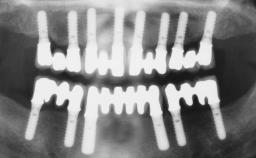

Immediate Loading of Four Implants in the Mandible and Final Restoration with a Full-Arch Metal Framework FDP

A fully edentulous 65-year-old woman was referred to our clinic for esthetic and functional dental rehabilitation. The patient presented with inadequate complete maxillary and mandibular prostheses, insufficient vertical dimension, and extensive tooth wear. The clinical examination and anamnesis showed no local or systemic contraindications, no signs or symptoms of bruxism, and an absence of smoking habits. The treatment proposed was implant placement in the mandibular interforaminal area and immediate loading with a fixed definitive prosthesis. A removable mucosa-supported complete prosthesis was indicated for the upper jaw, since its bone structure offered satisfactory retention and the financial condition of the patient disfavored a full-mouth implant-supported rehabilitation.

# of Implants 4

Type of Implants One-Piece

Defining Characteristics Fully edentulous lower jaw to be rehabilitated with two or more implants

Modality 3 or 4 interforaminal implants